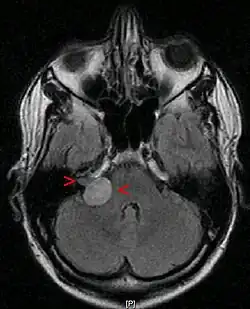

A ressonância magnética é a imagem de escolha, porque pode diferenciar com mais precisão a massa de outros tumores, como meningioma , schwannoma do nervo facial, cisto epidermóide, cisto aracnóide, aneurisma e metástase cerebral. A ressonância magnética também ajuda no planejamento cirúrgico e no acompanhamento do tumor após a cirurgia.[7]